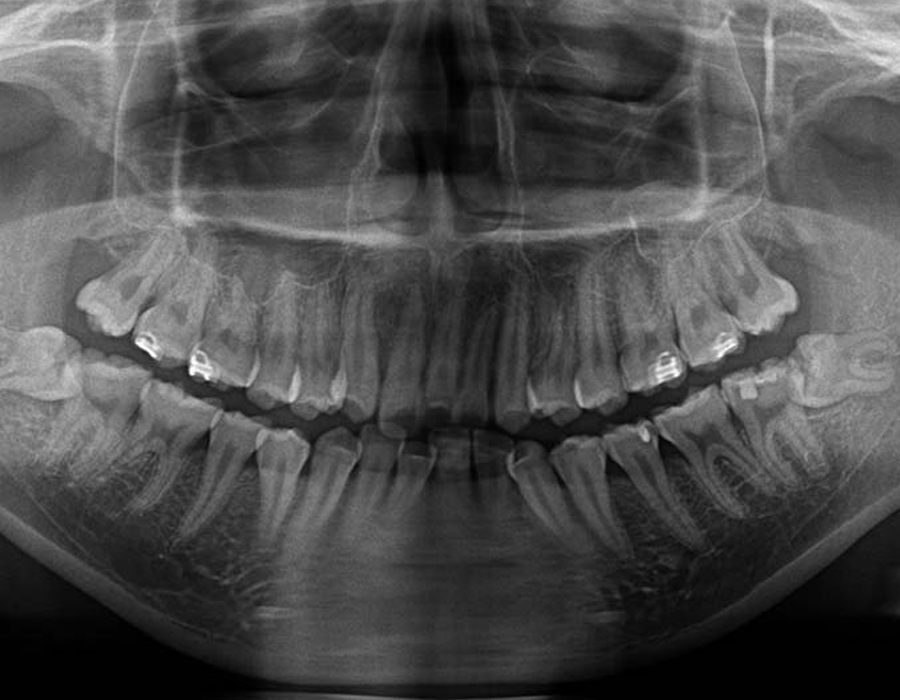

短時間で安全に親知らずを抜歯するためには、事前の画像検査が欠かせません。CT撮影により、親知らずや顎の骨の状態を詳しく知ることができます。その上でお口の中を拝見します。現状と歯科医としての意見をお伝えし、患者様と話し合いながら、抜歯を行うのか、残して経過観察に留めるか決定します。